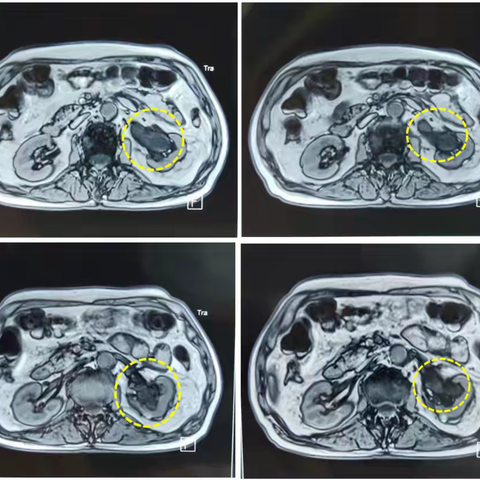

肾盂癌的放射性粒子植入治疗